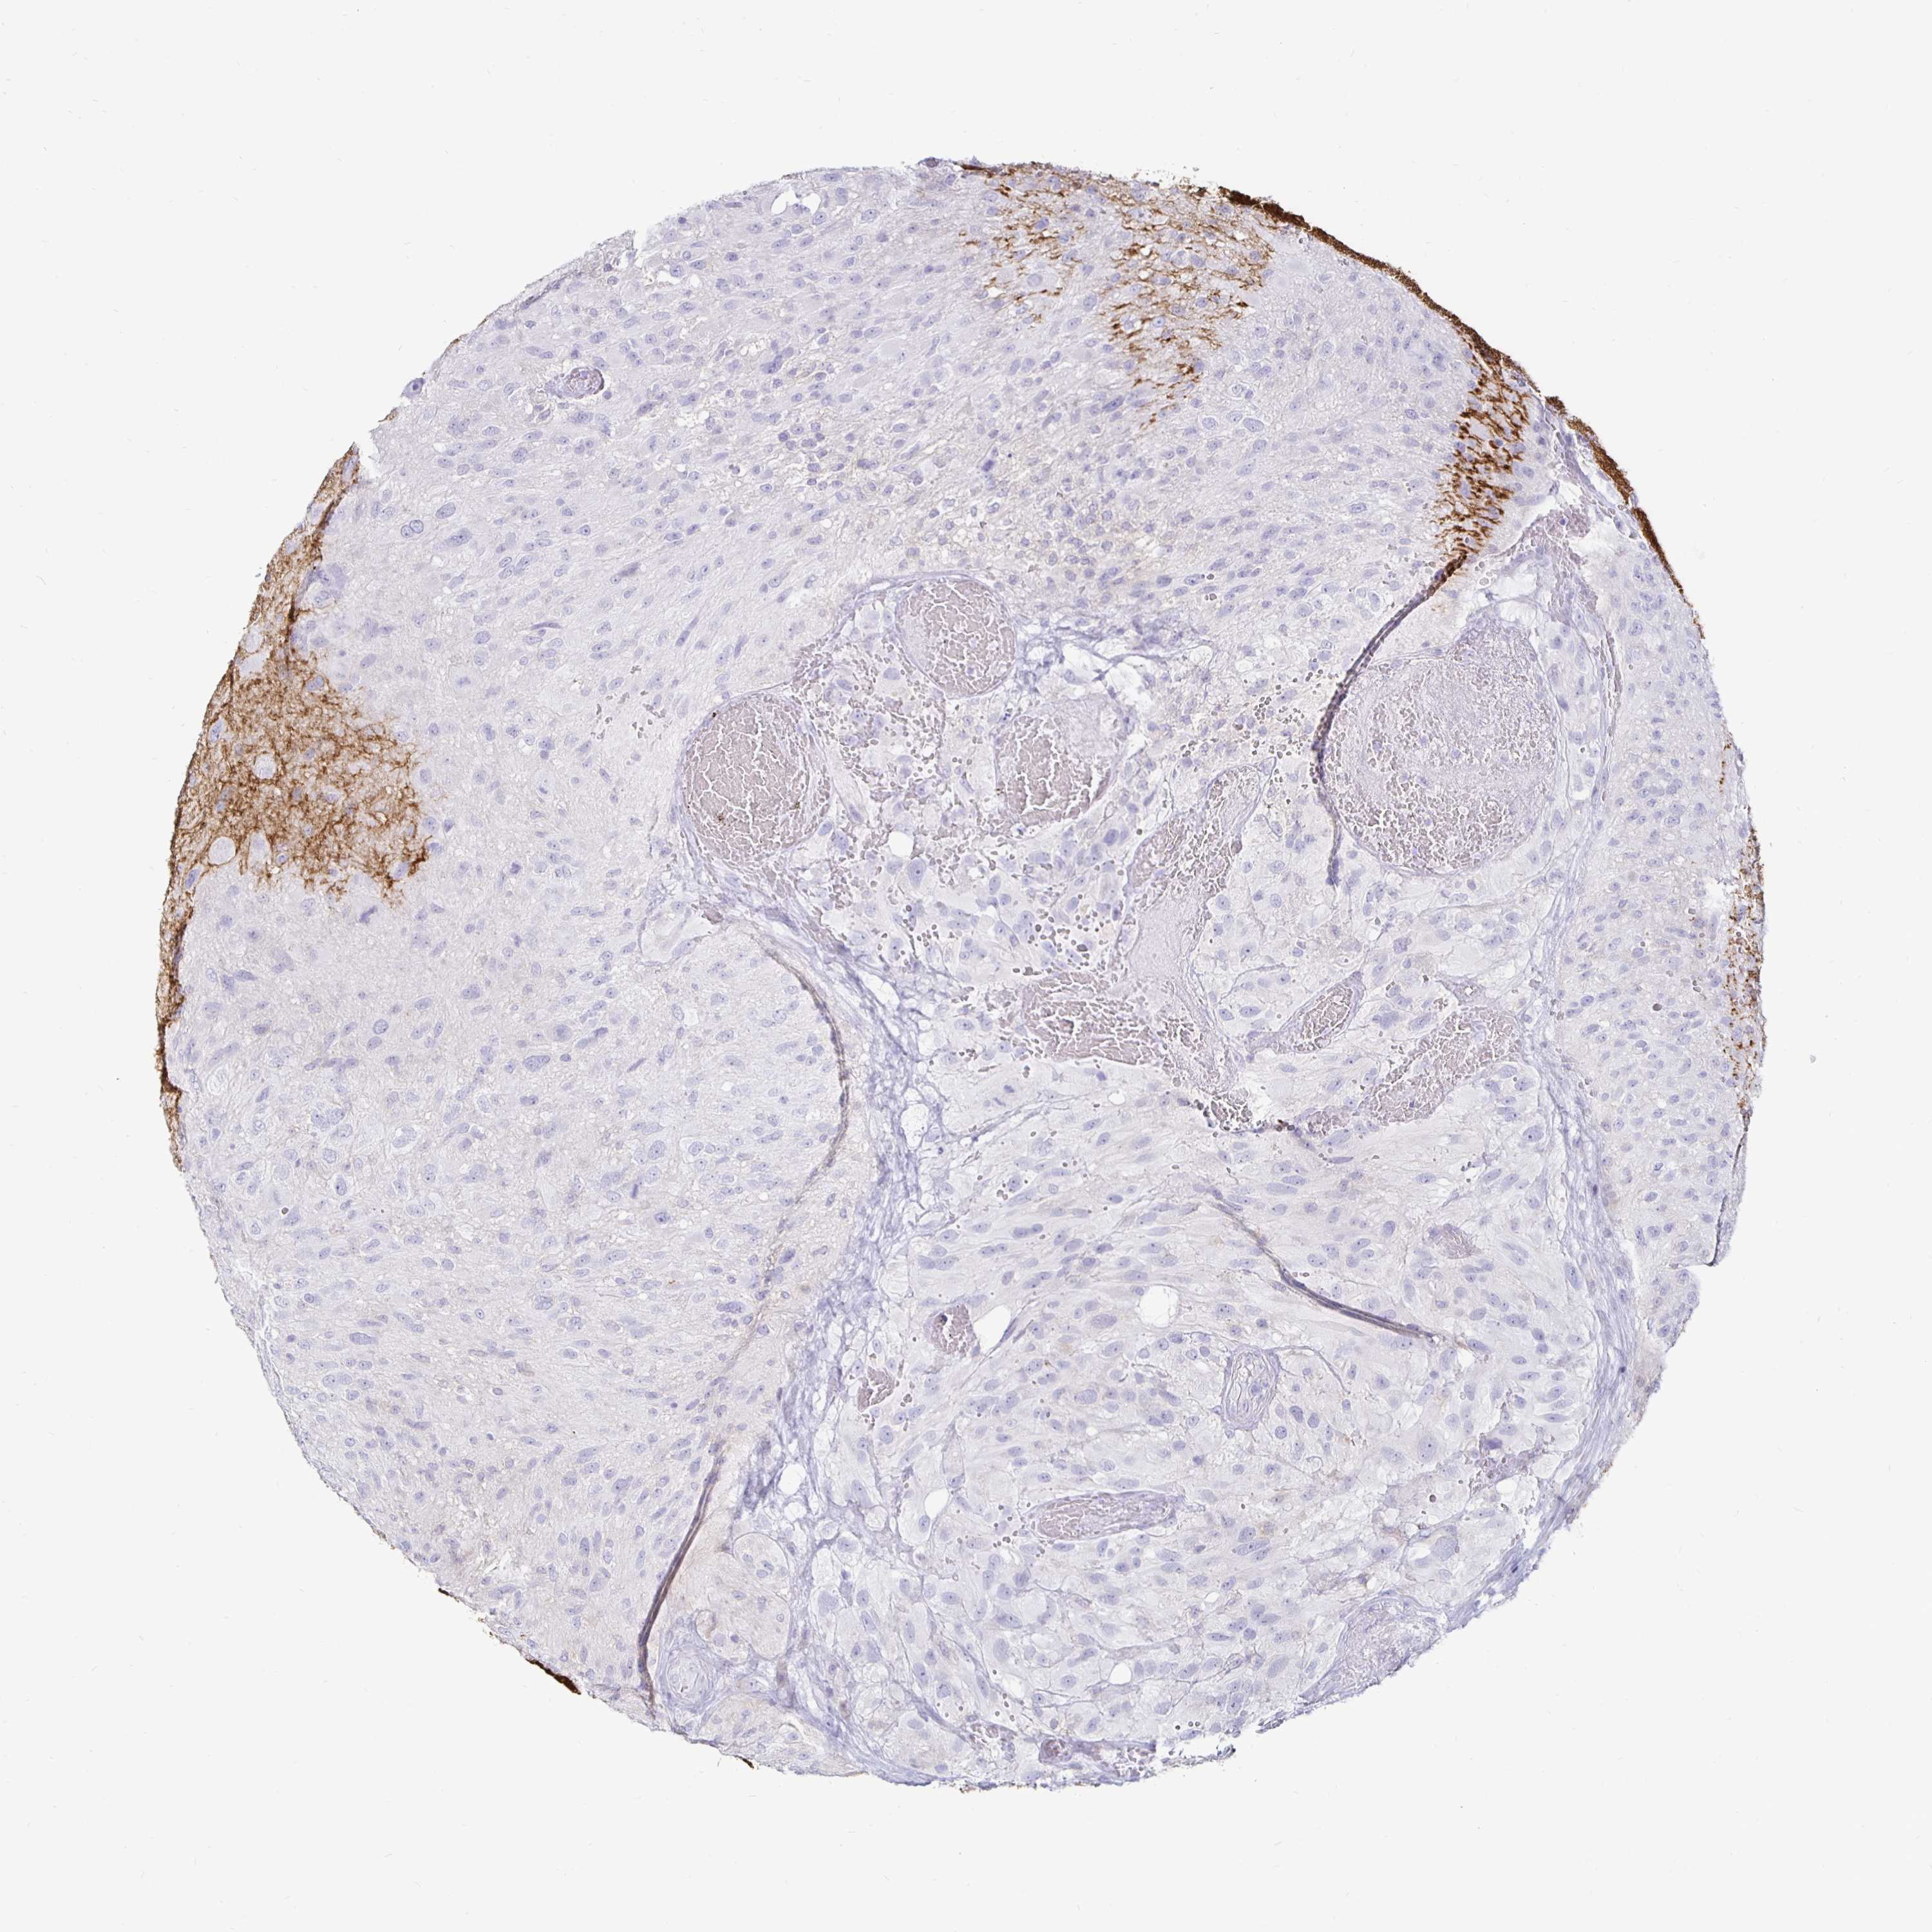

GLIOMA - Protein expressioni

A mouse-over function shows sample information and annotation data. Click on an image to view it in a full screen mode. Samples can be filtered based on level of antibody staining by selecting one or several of the following categories: high, medium, low and not detected. The assay and annotation is described here.

Note that samples used for immunohistochemistry by the Human Protein Atlas do not correspond to samples in the TCGA dataset.

Antibody stainingi

Antibody staining in the annotated cell types in the current human tissue is reported as not detected, low, medium, or high, based on conventional immunohistochemistry profiling in selected tissues. This score is based on the combination of the staining intensity and fraction of stained cells.

Each image is clickable and will lead to virtual microscopy that enables deeper exploration of all samples and also displays staining intensity scores, fraction scores and subcellular localization as well as patient and tissue information for each sample.

Antibody HPA054437

Antibody HPA058511

Antibody CAB002776

Antibody CAB015122

Glioma, malignant, Low grade

Glioma, malignant, High grade

Glioma, malignant, NOS